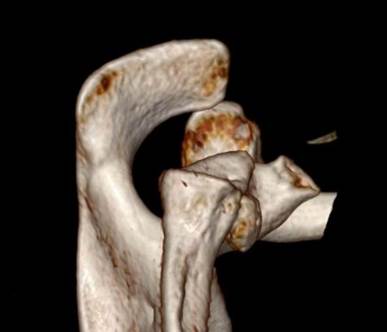

全镜下Bristow手术

在国际上首创关节镜下改良“嵌入式”喙突移位(Bristow)手术,并将其命名为CUIstow手术(Chinese Unique Inlay Bristow)

全镜下Latarjet手术